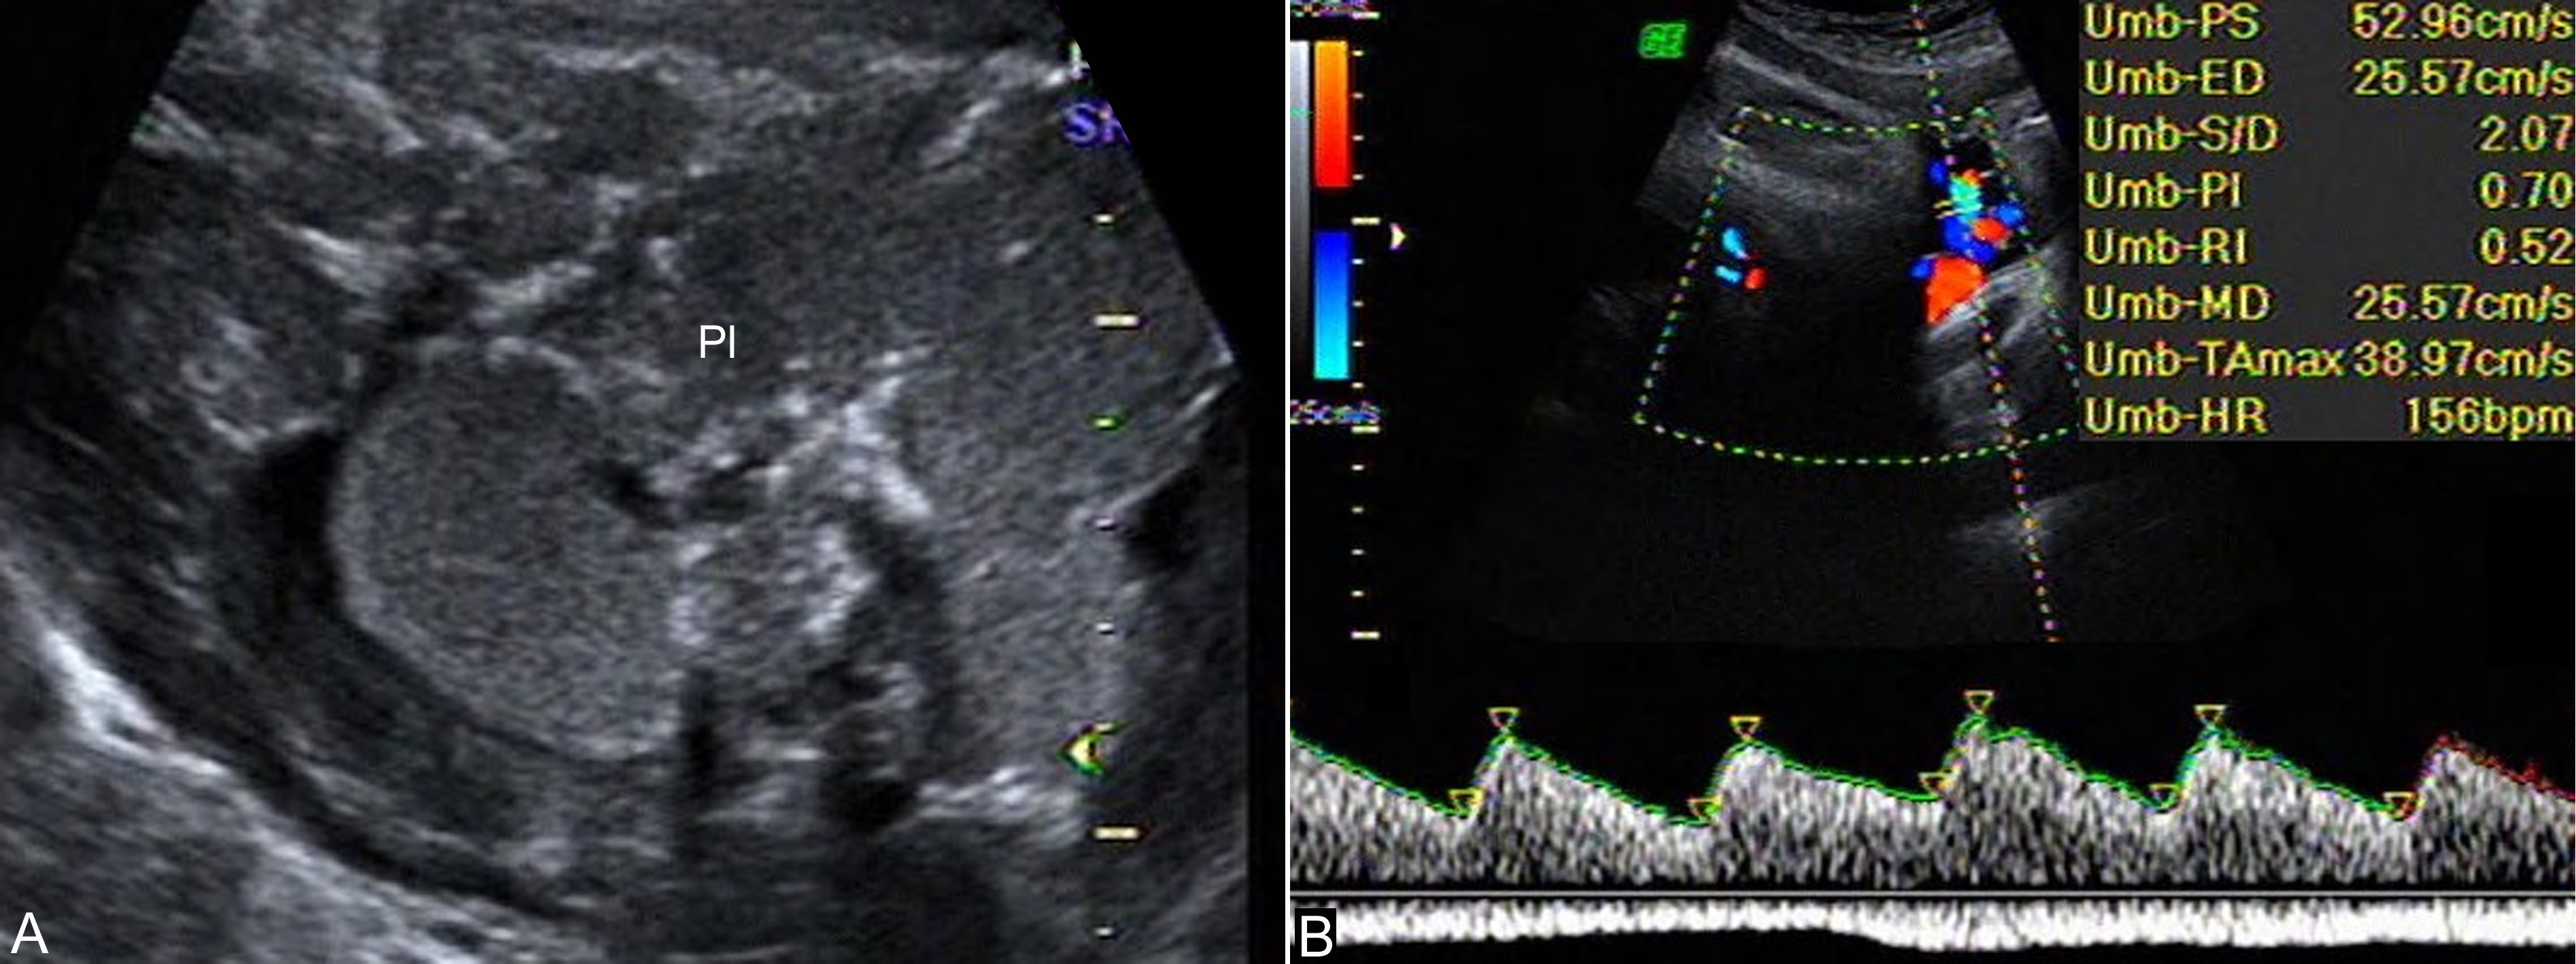

1.胎盘 超声显像检查显示Ⅲ级胎盘并不是胎盘老化、功能下降的征象,如果无其他证据并且胎头BPD>8.7cm时,常可以认为胎儿肺部已发育成熟。但过期妊娠时几乎均是Ⅲ级胎盘(图1A),这提示我们对于Ⅲ级胎盘的孕妇要排除过期妊娠的可能。Ⅲ级胎盘合并羊水过少和羊水浑浊,常提示胎盘功能低下,需要及时终止妊娠。

2.脐带 正常妊娠时胎盘血液循环随着妊娠月份的增加阻力逐渐下降,至妊娠40周时降至最低(图1B)。过期妊娠时由于胎盘血管床的减少和间质纤维化增加了胎盘血液循环阻力,脐带血流阻力增加,S/D升高。因此,超声多普勒检查过期妊娠的脐带血流时,如果发现S/D不再降低反而升高,则提示胎儿宫内缺氧,并且脐动脉S/D的异常多发生在胎儿缺氧引起的其他改变以前。

图25-22妊娠晚期胎盘及脐带血流:A:Ⅲ级胎盘声像图 B:正常脐带血流,S/D2.07